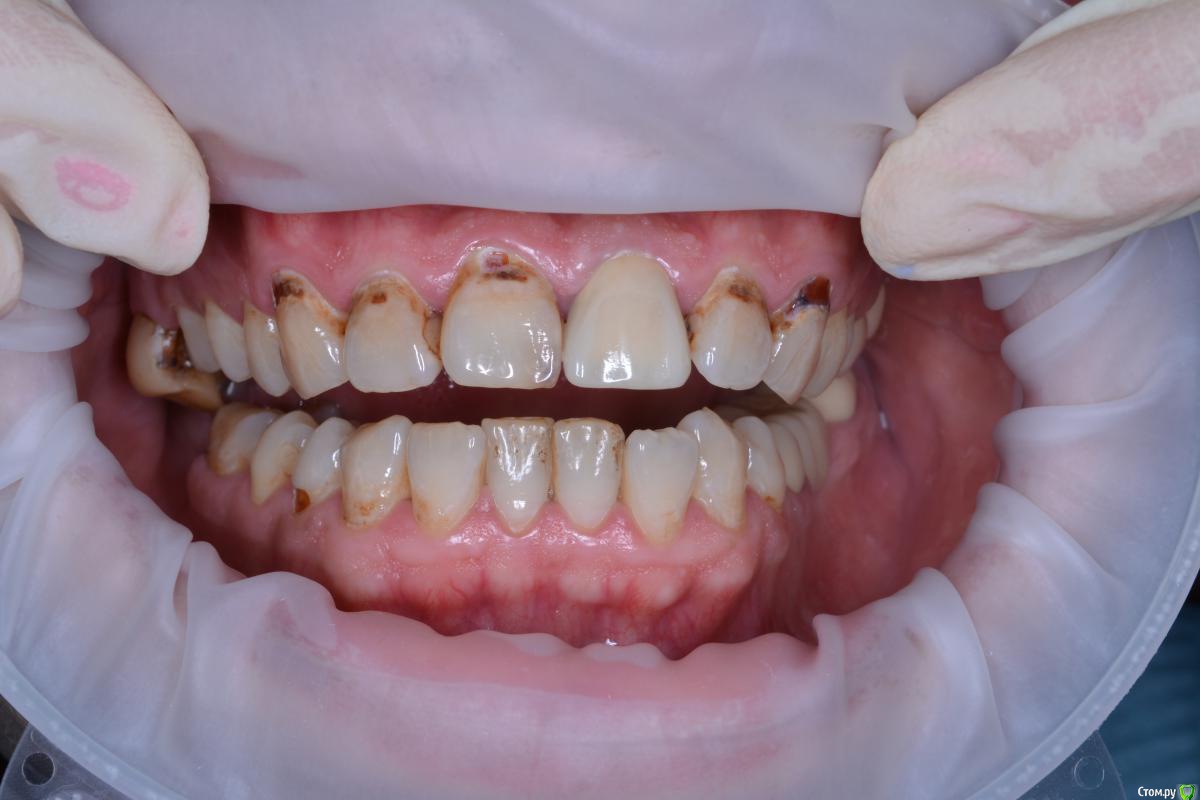

alekcandr ovs. Опубликовано 3 июля, 2017 Поделиться Опубликовано 3 июля, 2017 Планируется протезирование от 13---23 Получиться ли перекрыть цвет E.max??? может диоксид с нанесением??? Ссылка на комментарий

DmitrySH Опубликовано 3 июля, 2017 Поделиться Опубликовано 3 июля, 2017 Е.мах, кариес сперва полечите только. 1 Ссылка на комментарий

DR.P Опубликовано 3 июля, 2017 Поделиться Опубликовано 3 июля, 2017 (изменено) Сейчас, выполняю похожее лечение. Пролечил кариес этих флюорозных эрозий. Оттенок в тон культей. Все делал с коффердамом, получается ретракция платком и полное обнажение границ эрозий. Получилось отлично. После уже препарирование. Я выбрал виниры на рефракторе...но это потому что люблю его больше. Но так же можно сделать и на имаксе, думаю MO будет достаточно Изменено 3 июля, 2017 пользователем DR.P Ссылка на комментарий